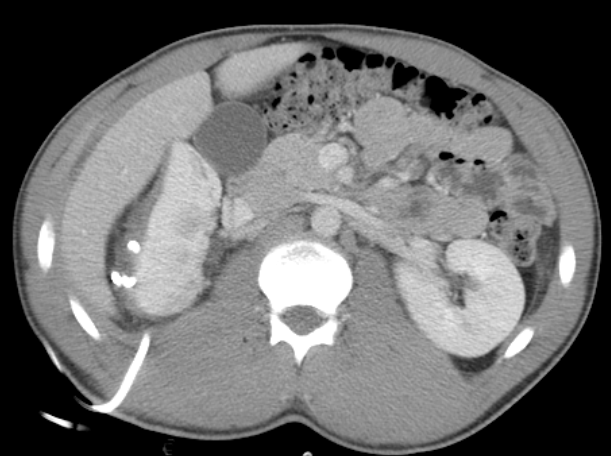

- New renal staging criteria